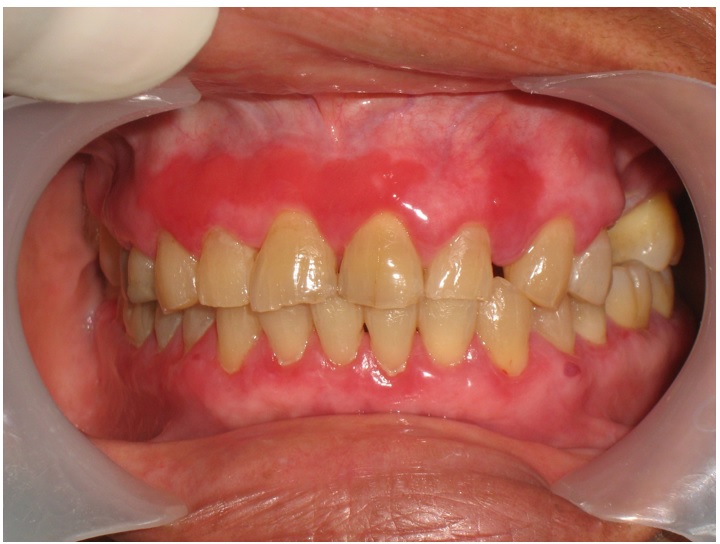

El LPO presenta varias manifestaciones clínicas que se clasifican como típico (reticular) y atípico (forma atrófica, en placa, erosiva, bullosa y mixta) (19). Durante la exploración y para su diferenciación clínica, hay que tener en cuenta el tipo de lesión, la localización, su bilateralidad y simetría (20,21). La variante más frecuente es la reticular, que se observa como manchas blancas, lineales en forma estrellada, de red o arboriformes (estrías de Wickham), que no se desprenden al ser raspadas. Se localiza especialmente en mucosa yugal de manera bilateral, simétrica y es asintomático (17,22,23).

La variante atípica atrófica se caracteriza por presentar zonas rojas atróficas en las que hay una solución de continuidad del epitelio. Se localiza frecuentemente en la lengua, la mucosa yugal, la encía, el fondo de surco de la mucosa labial y el piso de la boca. Cuando se presenta en la mucosa yugal, las lesiones pueden ser bilaterales (figura 2). En la forma atípica erosiva se presentan erosiones de cloro rojo intenso a veces sangrantes, localizadas en cualquier sitio de la mucosa oral. También se aprecian ulceraciones. La sintomatología es característica. Esta forma clínica es la que con mayor frecuencia puede sufrir transformación maligna hacia un carcinoma escamocelular (17,24,25).